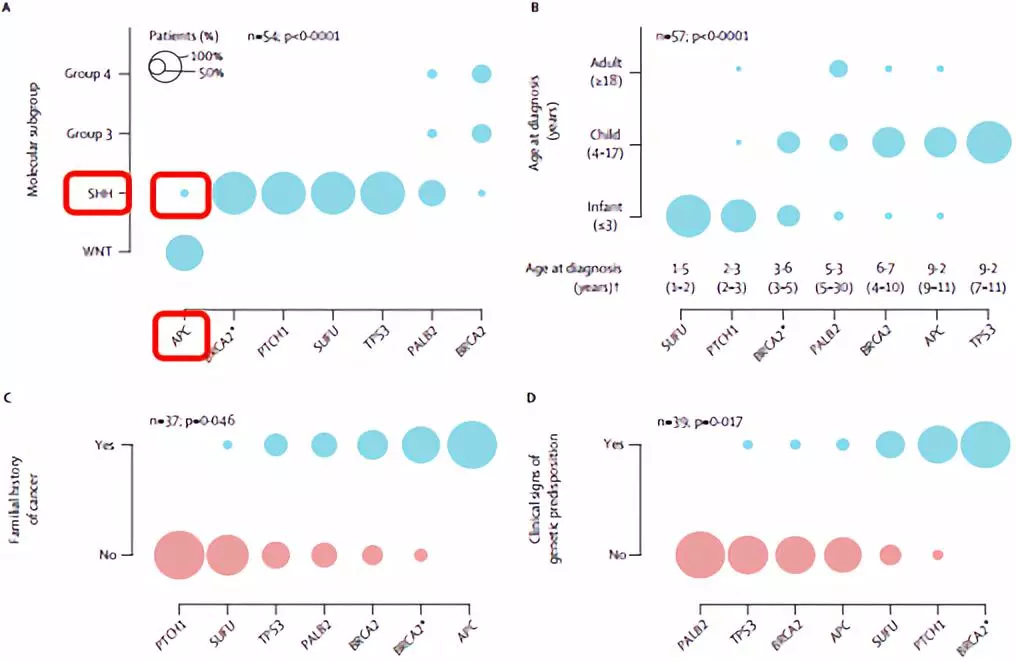

结合WHO中枢神经系统肿瘤分类指南(2016),基因检测结果显示:患者属于髓母细胞瘤, SHH激活及TP53野生型(图3、图4、图5)。分子评估其危险等级倾向于标危,需结合临床共同判断文献报道预后的5年中位总生存率为76%,但有APC遗传可能有其他肿瘤发生的风险。

本案例肿瘤特点及预后提示:本案例基因检测结果在发现其髓母细胞瘤细胞分型为SHH激活型TP53野生型的同时,还发现了APC胚系突变。APC突变在WNT型髓母细胞瘤中较多见,但在SHH型中罕见,应注意防范其他瘤种的发生。SHH型中常见的其他基因遗传性突变有TP53突变、PTCH1突变、SUFU突变等,相关的遗传性综合征有Li-Fraumeni 综合征和Gorlin 综合征。此外,APC突变通常具有家族史,因此根据基因检测结果,建议其父母也同步进行基因检测,如果携带遗传变异,发生某些肿瘤风险会显著升高,需定期关注。该基因的某些遗传性突变与APC相关息肉综合征的患病风险相关,包括家族性腺瘤性息肉瘤(familial adenomatous polyposis,FAP)、轻表型FAP、Gardner综合征、Turcot综合征和衰减型家族性腺瘤性息肉瘤;相关癌症包括:结直肠癌,胰腺癌,胃癌,小肠癌,硬纤维瘤,甲状腺癌,肝癌,中枢神经系统肿瘤。

图6. 文献表明APC突变少量发生在SHH型中